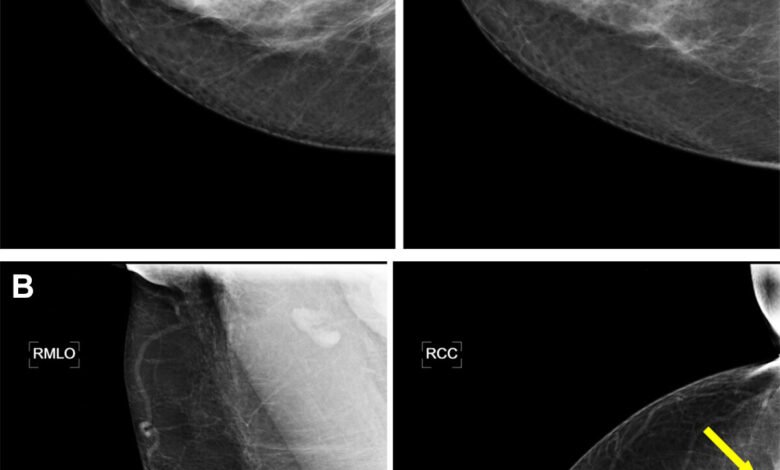

Exemplo de mamografia de triagem com um carcinoma ductal agressivo (seta), no qual as mulheres não teriam sido lembradas com uma estratégia de cavalia de leitura de AI. No entanto, esses exames teriam sido mostrados ao radiologista em uma estratégia de leitura híbrida, que será baseada na incerteza da IA da entrada da pontuação maliciosa da área (POM) da área mais suspeita. Para ambos os exames, são mostradas idéias medievais (esquerda) e cranochel (à direita) da mama afetada. (A) Imagens em uma mulher de 67 anos, que foram lembradas porque ambos os radiologistas pontuaram a mama direita como relatório de imagens de mama e sistema de dados (BI-BI-REDS) 0. A mulher não teria sido lembrada se o exame fosse lido pelo modelo de IA, que foi atribuído a uma pontuação de 40, mas a previsão teria sido classificada como uma incerteza com uma incerteza. (B) Imagens em uma mulher de 63 anos que foram lembradas quando os dois radiologistas fizeram os seios certos como BI-Reds 4. A mulher não teria sido lembrada se o exame fosse lido pelo modelo de IA, com uma pontuação de 44 POM, mas a previsão seria classificada como uma previsão incerta, que seria classificada com uma previsão de uma incerteza. Crédito: Sociedade Radiológica da América do Norte (RSNA)